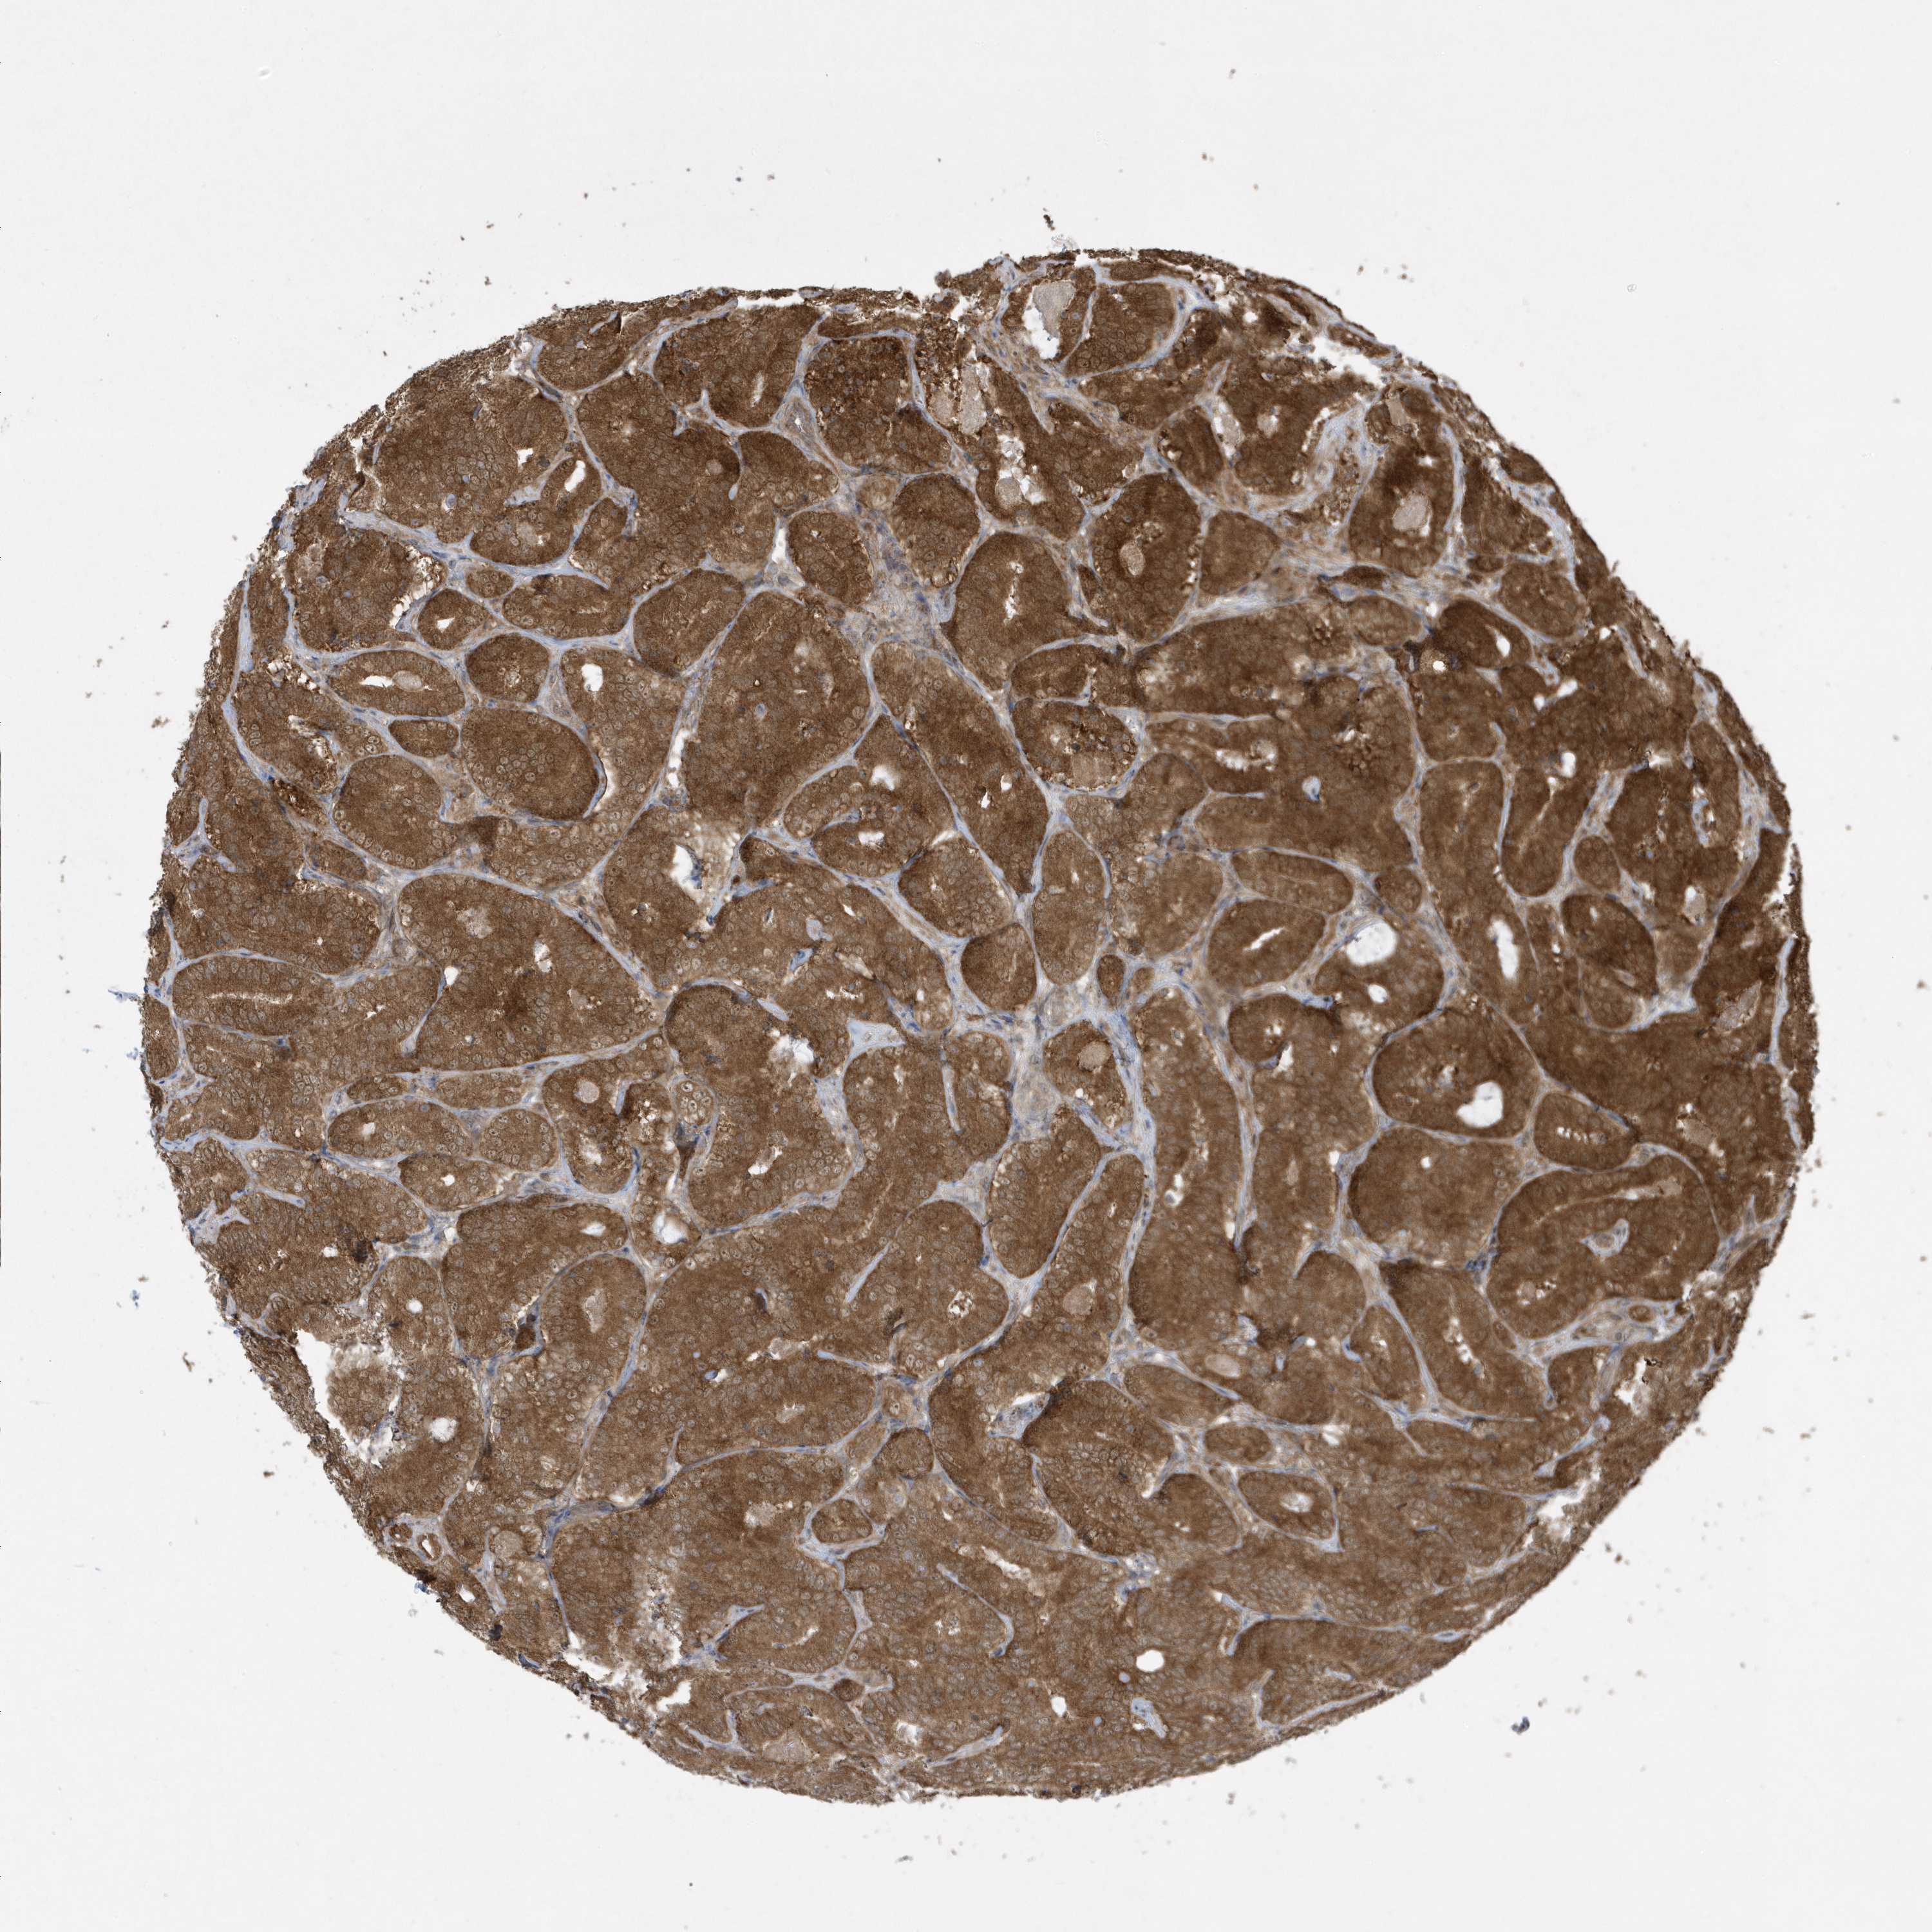

PROSTATE CANCER - Protein expressioni

A mouse-over function shows sample information and annotation data. Click on an image to view it in a full screen mode. Samples can be filtered based on level of antibody staining by selecting one or several of the following categories: high, medium, low and not detected. The assay and annotation is described here.

Note that samples used for immunohistochemistry by the Human Protein Atlas do not correspond to samples in the TCGA dataset.

Antibody stainingi

Antibody staining in the annotated cell types in the current human tissue is reported as not detected, low, medium, or high, based on conventional immunohistochemistry profiling in selected tissues. This score is based on the combination of the staining intensity and fraction of stained cells.

Each image is clickable and will lead to virtual microscopy that enables deeper exploration of all samples and also displays staining intensity scores, fraction scores and subcellular localization as well as patient and tissue information for each sample.

Antibody HPA035800

Staining

High

Medium

Low

Not detected

Intensity

Strong

Moderate

Weak

Negative

Quantity

>75%

75%-25%

<25%

None

Location

Nuclear

Cytoplasmic/membranous

Cytoplasmic/membranous,nuclear

Adenocarcinoma, High grade

Adenocarcinoma, Low grade